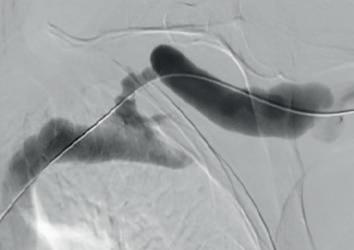

Example procedural outcome: treatment of Bond’s patient with a left brachiocephalic AVF that presented with a stenosis at the cephalic arch with aneurysmal segment.

(A) Fistulogram taken preintervention and (B) after deployment of WRAPSODY to treat. (C) Fluoroscopy of treated segment at 18 months (D) and patient’s arm at time of presentation

Bond was the first in the world to commercially implant Wrapsody CIE three years ago. “The first patient I remember well,” he says. “She had a left brachiocephalic fistula that had been put in place in 2014, and it had been working in the two years before I saw her in 2019. The main problem was that she was getting a lot of pain when the AVF was used for haemodialysis, and it was taking five to six hours to dialyse.” He adds that she “experienced bleeding from the fistula following dialysis.”

Bond explains that she was diagnosed with a particularly tight cephalic arch stenosis. Despite four previous treatment attempts by the radiology team rapid restenosis of her cephalic arch occurred each time. With her referral to Bond and the renal team, the initial treatment plan was to ligate the fistula. However, Bond opted for the Wrapsody CIE instead.